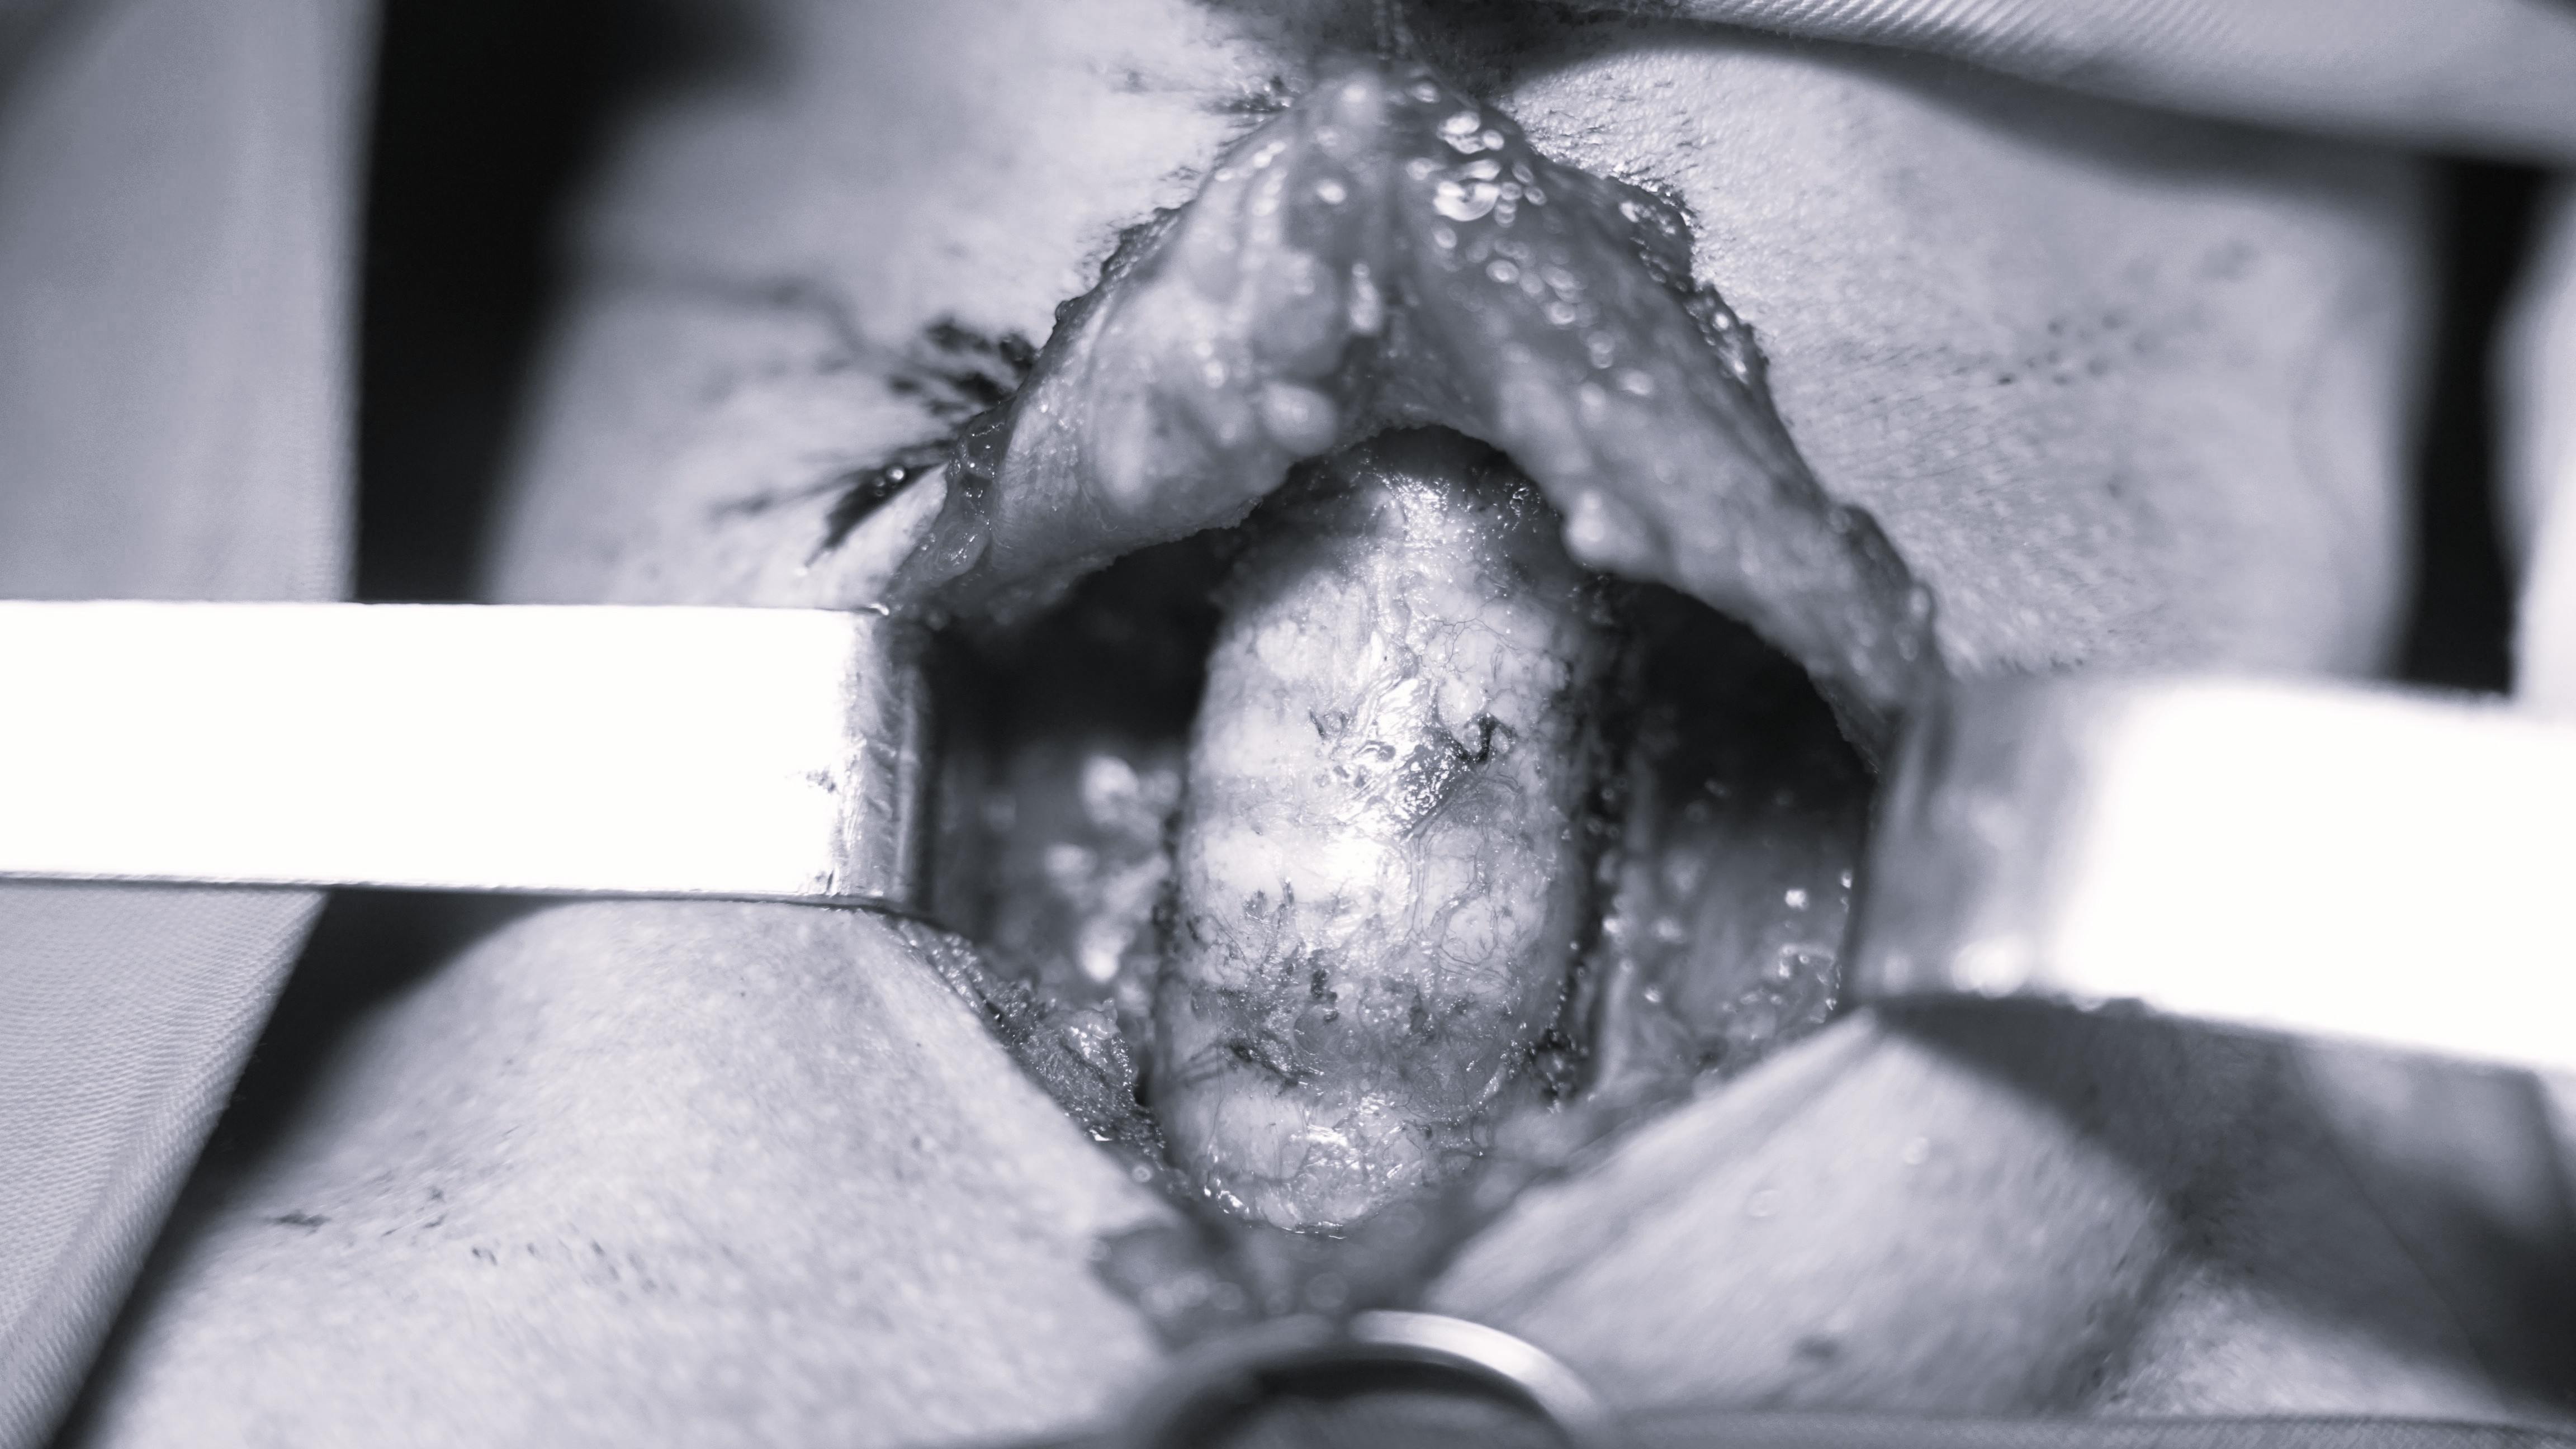

Tại đây người bệnh được thăm khám, xét nghiệm Tế bào học chọc hút kim nhỏ (FNA) kết luận: Hình ảnh phù hợp ung thư biểu mô tuyến giáp; làm đầy đủ xét nghiệm chẩn đoán bệnh, giai đoạn bệnh, đặc biệt có siêu âm bản đồ hạch trước phẫu thuật. Người bệnh được chỉ định phẫu thuật và sinh thiết tức thì trong mổ, kết quả ung thư hai thùy tuyến giáp. Chỉ định cắt toàn bộ tuyến giáp và vét hạch trung tâm.

Ca phẫu thuật thành công nhờ sự phối hợp chặt chẽ của ekip phẫu thuật do BS.CKI. Đỗ Việt Dũng, Phụ trách khoa Ung Bướu, Bệnh viện A – với trên 10 năm kinh nghiệm điều trị các bệnh lý ung thư trực tiếp đảm nhận phẫu thuật chính. Kết quả đã phẫu thuật triệt căn, nạo vét hạch loại bỏ sạch bệnh tích và vẫn giữ được các tuyến cận giáp, đồng thời bảo tồn trọn vẹn dây thần kinh thanh quản quặt ngược, giữ giọng nói cho bệnh nhân. Sau phẫu thuật người bệnh ổn định và tiếp tục điều trị hậu phẫu, không tai biến gì.

Phẫu thuật triệt căn và nạo vét sạch hạch theo bản đồ hạch lập trước mổ